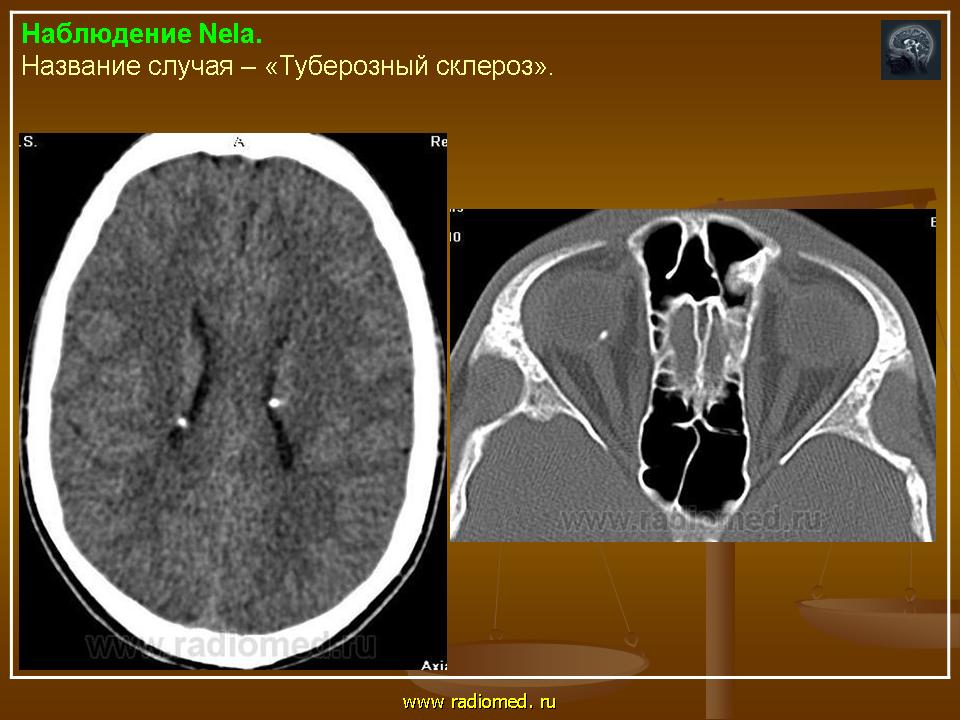

Туберозный склероз, или синдром Бурневиля - Прингля.

Приложения:

1.tu_.slayd184.jpg2.tu_.slayd185.jpg

Встречаются и аномалии развития извилин мозга в виде микро- и пахигирии. Заболевание чаще носит спорадический характер. Бляшки достигают диаметра 5-20 мм. В коре больших полушарий и мозжечка иногда могут быть обнару­жены пластинчатые тельца, напоминающие амилоид. Происходит дегенерация клеток коры. При КТ-исследовании головы нередко можно выявить кальцифика-ты и глиальные узелки в паравентрикулярной области, субэпендимарно вдоль на­ружных стенок боковых желудочков, в зоне межжелудочкового отверстия Мон­ро, реже - в мозговой паренхиме. На М РТ головного мозга в 60% выявляются гипотеденсивные очаги в одной или обеих затылочных долях, которые расце­ниваются как участки неправильной миелинизации (Козлов А.В., 2002).

Туберозный склероз в сочетании с фиброзной дисплазией

http://www.ajnr.org/content/24/5/835.full